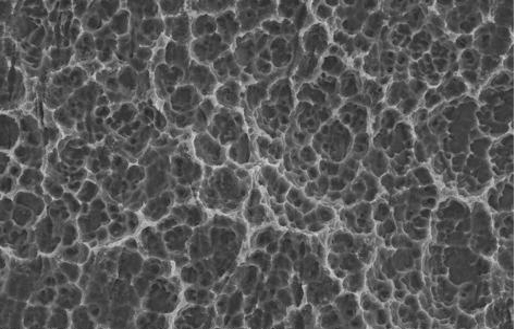

Topografía de superficie híbrida contemporánea (gruesa y fina)

Micrométrica fina 2000 X

Superficie micrométrica fina:

En el cuello la superficie del implante es Osseotite® (grabado ácido doble), lo que permite una protección contra la periimplantitis. Tiene rugosidades micrométricas finas que van de 1 a 3 micras.